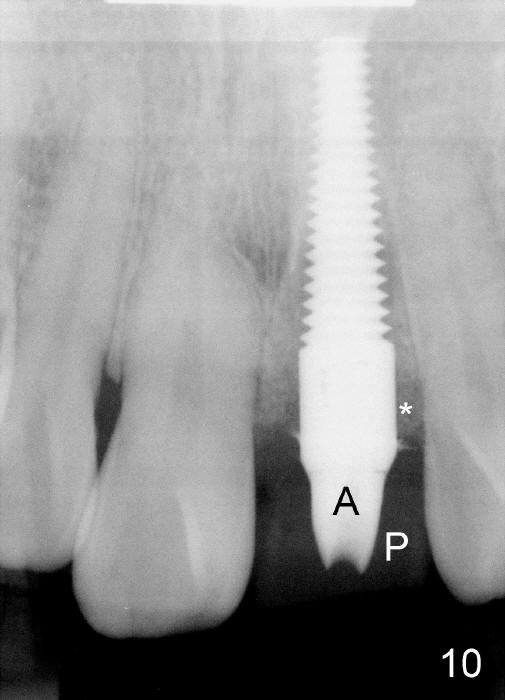

Bone expansion allows the implant (Fig.9 I) to have primary stability (insertion torque between 50 and 60 Ncm), since the cortex of the incisive canal is apparently intact.  Allograft is placed in the labial gap (Fig.10, 11 *) following installation of the abutment (A).  Finally an immediate provisional (Fig.10,12 P) is cemented.  Fig.13,14 are taken 8 days postop.  The patient returns 3 months postop (Fig.15,16).  Osteointegration appears to have occurred (Fig.15 arrowheads) and is more obvious 9 months postop (Fig.17).